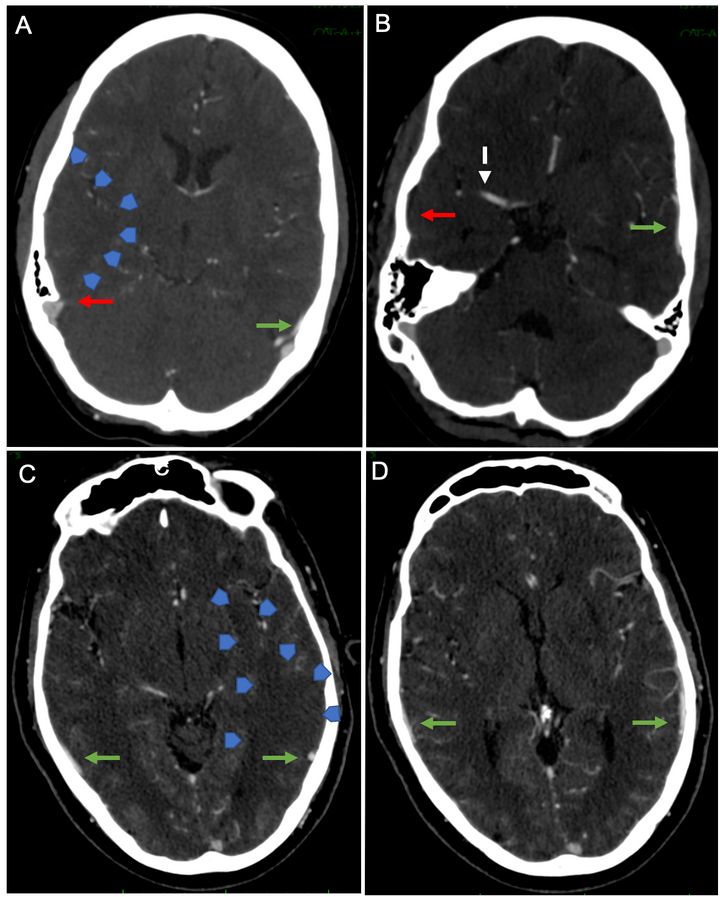

Computed Tomography-Based Imaging Algorithms for Patient Selection in Acute Ischemic Stroke

Pulli B, Heit JJ, and Wintermark M (2021) Neuroimaging Clin N Amer May;31(2):235-250. doi: 10.1016/j.nic.2020.12.002.Epub 2021 Mar 23.

Venous Outflow Profiles Are Linked to Cerebral Edema Formation at Noncontrast Head CT after Treatment in Acute Ischemic Stroke Regardless of Collateral Vessel Status at CT Angiography

Faizy T, et al. (2021) Radiology Apr 6;203651. doi: 10.1148/radiol.2021203651. Online ahead of print.

Non-contrast dual-energy CT virtual ischemia maps accurately estimate ischemic core size in large-vessel occlusive stroke

Wolman DN, et al. (2021) Scientific Reports Mar 24;11(1):6745. doi: 10.1038/s41598-021-85143-3.

Perfusion imaging-based tissue-level collaterals predict ischemic lesion net water uptake in patients with acute ischemic stroke and large vessel occlusion

Faizy T, et al. (2021) JCBFM Feb 8;271678X21992200. doi: 10.1177/0271678X21992200.

Automated Cerebral Hemorrhage Detection Using RAPID

Heit JJ, et al. (2021) AJNR Jan;42(2):273-278. doi: 10.3174/ajnr.A6926. Epub 2020 Dec 24.

CT perfusion core and ASPECT score prediction of outcomes in DEFUSE 3

Kim-Tenser M, et al. (2020) Int J Stroke Mar 31;1747493020915141. doi: 10.1177/1747493020915141.